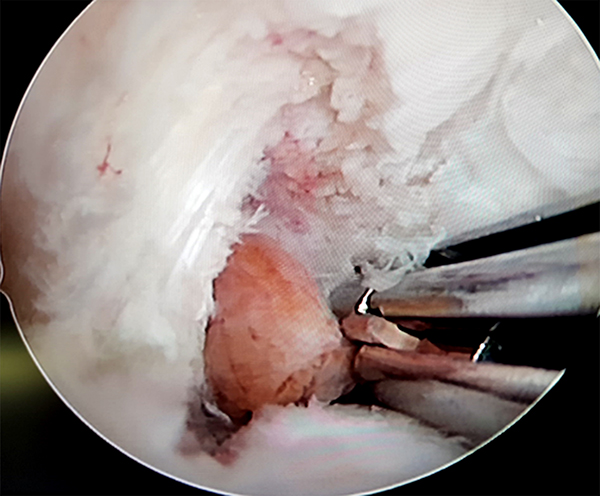

El paciente fue derivado al equipo de artroscopia de rodilla para evaluar la resección artroscópica de la misma. Se realizaron tres portales. El portal AL y AM estándar con objetivo el desbridamiento periférico en región anterior con preservación marginal. El portal PM con el objeto del desbridamiento periférico posterior y la exéresis en bloque de la pieza, lo cual se logro sin dificultad ni necesidad de realizar artrotomía (figs. 3, 4 y 5).

Figuras 3, 4 y 5: Superior derecha e izquierda: Se observa visión artroscópica por portal anterolateral y posteromedial, localización retro LCP. Inferior: Visualización artroscópica posterior a exéresis completa.

La anatomía patológica intraoperatoria reveló márgenes libres y confirmo el diagnostico de TCG (fig. 6).